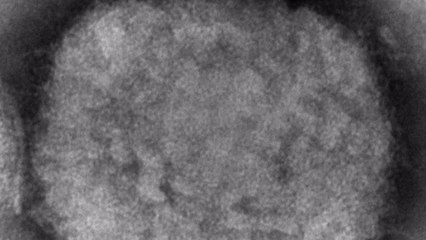

원숭이두창이 유럽·미주 등 비풍토병 지역에서 빠르게 번지며 한 달 만에 확진 건수가 천 건을 넘어섰습니다. br br 세계보건기구, WHO는 29개국에서 원숭이두창 감염 사례가 확인됐다며 일부 국가들에서 풍토병화될 징후를 보이고 있다고 경고했습니다. br br 김진호 기자의 보도입니다. br br [기자] br WHO는 원숭이두창이 비풍토병인 29개 국가에서 천 명이 넘는 확진자가 보고됐다고 밝혔습니다. br br WHO는 이러한 확진자 통계를 공개하며 일부 국가에서 풍토병이 될 위험이 있다고 전망했습니다. br br [테워드로스 거브러여수스 WHO 사무총장 : 원숭이두창이 비풍토병인 국가에서 풍토병으로 자리 잡을 위험은 현실입니다. WHO는 특히 어린이와 임신부 등 취약 집단에 대한 이 바이러스의 위험에 대해 우려하고 있습니다.] br br 거부러여수스 사무총장은 비풍토병 국가에서는 사망자가 보고되지 않았지만 아프리카에서는 올해들어 60명이 넘는 사망자가 나왔다는 점도 명심해야 한다고 강조했습니다. br br 그는 또 일부 국가에서는 지역 전파가 진행 중이라는 징후가 있다며 감염자의 자가격리를 권고했습니다. br br 천연두와 증상이 비슷한 원숭이두창은 중·서부 아프리카에서 풍토병화된 바이러스입니다. br br 하지만 지난달 7일 영국에서 감염 사례가 나온 이래 유럽과 미주·중동·호주 등에서 잇따라 확진자가 발생해 또 다른 보건 위기가 오는 것이 아닌가하는 우려를 불러왔습니다. br br 지금까지는 동성과 성관계를 가진 남성 사이에서 감염 사례가 두드러집니다. br br [로자문드 루이스 WHO 긴급 대응 프로그램 천연두 사무국장 : 현재 비풍토병적인 환경에서 보고되고 있는 사례들은 주로 동성과 성관계를 가진 남성들 사이에서 발생하고 있습니다.] br br WHO는 많지는 않지만 여성 확진자도 보고되고 있다고 밝혔습니다. br br 루이스 사무국장은 타인과의 밀접 접촉이 주된 전파 경로라고 재차 강조하면서 공기로 전파되고 있는지에 대해선 아직 확인된 바 없다고 설명했습니다. br br YTN 김진호입니다. br br br br br br YTN 김진호 (jhkim@ytn.co.kr)br br ※ '당신의 제보가 뉴스가 됩니다' br [카카오톡] YTN 검색해 채널 추가 br [전화] 02-398-8585 br [메일] social@ytn.co.krbr br ▶ 기사 원문 : ▶ 제보 안내 : , 모바일앱, social@ytn.co.